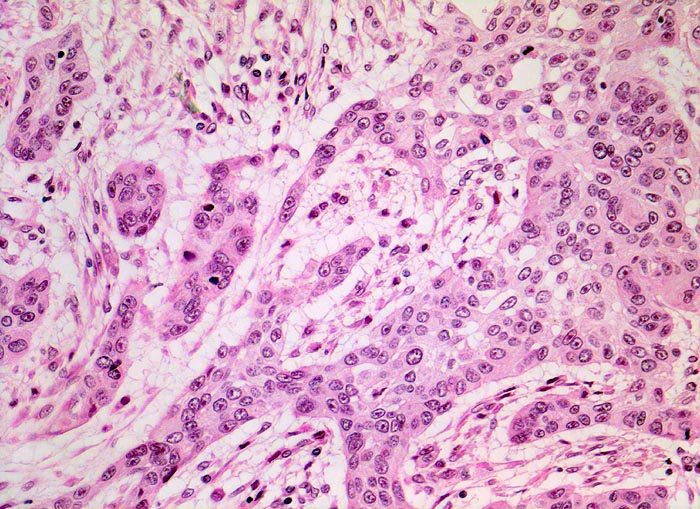

Morphologische Merkmale:

• Polypoides exophytisches Karzinom.

• Tumordurchbruch durch die Lamina muscularis mucosae in die Submukosa.

• Der Tumor bildet anastomosierende solide Zellstränge, die fokal im Zentrum verhornen.

• Tumorzellen mit reichlich glasigem eosinophilem Zytoplasma und scharfen Zellgrenzen mit stachelförmigen Interzellularbrücken. Stark vergrösserte, pleomorphe, hyperchromatische Zellkerne mit prominenten Nukleolen.

• Zwischen den Tumorzellsträngen desmoplastisches Stroma mit dichtem gemischtem Entzündungsinfiltrat.

• Präneoplastisch veränderte Mukosa im Randbereich des Karzinoms mit ausgeprägten Zellatypien in der gesamten Epithelbreite und zahlreichen Mitosen (Carcinoma in situ).